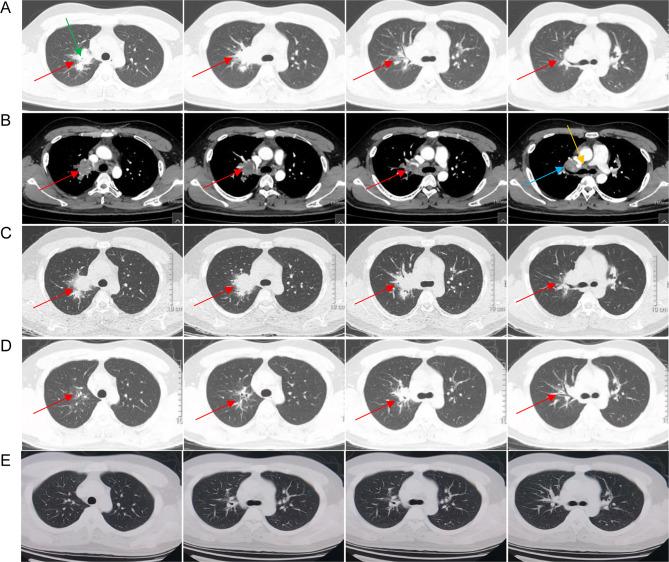

is a nonpathogenic pathogen commonly found in nature and is generally considered a contaminant in clinical practice. Although there have been few reported cases of infection, most of them are secondary to immunosuppression. This paper described a rare case of globular shadow in the chest of an immunocompetent male who was diagnosed with pulmonary disease. He went to the hospital with chest pains that had lasted for more than two weeks. The routine clinical pathogen detection failed to discover the cause of the infection. Although metagenomic next-generation sequencing (mNGS) of the lung tissue was negative, was detected in the background microorganism with only one read. Based on the pathological results, it was considered to be the causative pathogen. Two months of treatment with rifampicin, ethambutol, clarithromycin, and levofloxacin resulted in significant reduction and absorption of lung lesions. No abnormalities were detected in either lung one year later. The lack of positive culture and other conventional microbiological test results make this case is not a strictly confirmed case. This study also explored the clinical features and treatment options of 32 cases of pulmonary disease through a systematic review of the literature. Although there is no standard recommended treatment regimen for infection, but combination therapy with macrolides, rifampicin, and ethambutol has been proven effective.

是一种常见于自然界的非致病性病原菌,在临床实践中通常被视为污染物。虽然报道的感染病例很少,但其多数继发于免疫抑制。本文描述了一例免疫功能正常男性胸部出现球形阴影,被诊断为肺病的罕见病例。他因胸痛持续两周以上前往医院就诊。常规临床病原体检测未能发现感染原因。尽管肺组织的宏基因组下一代测序(mNGS)结果为阴性,但在背景微生物中仅检测到一条 reads 的该菌。基于病理结果,认为其为致病病原体。使用利福平、乙胺丁醇、克拉霉素和左氧氟沙星治疗两个月后,肺部病变明显减轻并吸收。一年后双肺均未检测到异常。由于缺乏阳性培养及其他常规微生物检测结果,该病例并非严格意义上的确诊病例。本研究还通过系统回顾文献,探讨了32例肺病的临床特征及治疗选择。虽然对于感染尚无标准推荐治疗方案,但大环内酯类、利福平和乙胺丁醇联合治疗已被证明有效。